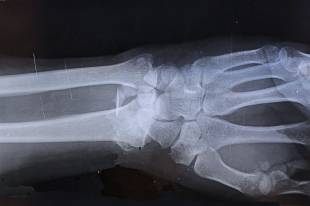

작은 충격에도 골절 위험이 커지는 이유는 겉보기엔 멀쩡해도 속이 비워지는 속도가 빨라지기 때문입니다. 뼈는 단단한 성벽 같지만, 안쪽 돌이 하나둘 빠지면 작은 충격에도 균열이 번집니다. 특히 척추 압박골절이 흔해 키가 줄거나 갑작스러운 움직임 뒤에 심한 불편이 생길 수 있습니다.

혈액 및 영상검사에서 칼슘 상승, 다발성 골병변이 함께 보이면 위험도가 더 올라갑니다. 골절은 넘어짐 같은 큰 사건이 아니라, 물건을 들거나 허리를 비트는 생활 동작에서 시작될 수도 있습니다. 따라서 통상적인 골다공증과 같은 선상에만 두지 말고, 원인 질환이 만든 구조적 약화를 함께 고려해야 합니다.